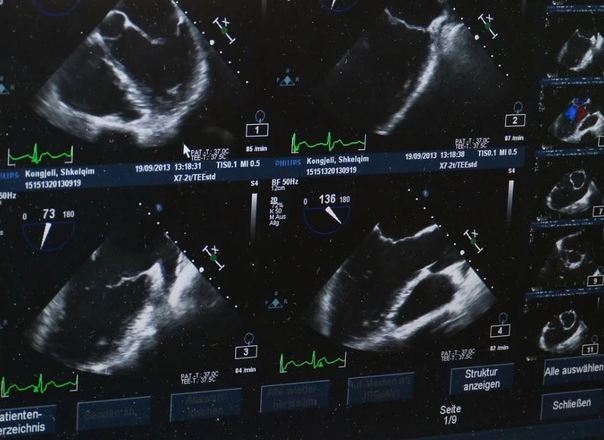

Grávida fica chocada com imagem sinistra do filho no ultrassom

Uma mãe grávida ficou um tanto surpresa e chocada quando viu o filho encarando a câmera de uma forma um tanto sinistra

Jo Greer, 34 anos, mora em Plymouth (Reino Unido) e está grávida de 20 semanas, e foi fazer o exame para saber se está tudo bem com a criança

Mas aconteceu algo um tanto raro e até assustador: a criança olhou para a câmera

Apesar do choque da primeira reação, Jo afirma que a imagem a divertiu depois

"Foi bastante assustador, foi um choque. Mas depois, eu e meu parceiro apenas nos viramos um para o outro e caímos na gargalhada", conta ela para o tabloide inglês The Sun

"Aparentemente, não há nada de errado com isso, mas nos disseram que é bastante raro que o bebê olhe para a câmera"

Os dois estão mantendo a surpresa sobre o sexo do bebê e já sabem o que farão com a foto da criança encarando a câmera

Eles irão imprimir e dar para o filho quando ele fizer 18 anos

"Vamos manter a imagem e colocá-la no cartão de aniversário de 18 anos como uma risadinha"

Uma mãe adolescente passou por situação semelhante no meio de um ultrassom. Ela viu o que parecia ser um "rosto alienígena" nas imagens. Veja a seguir!

A adolescente Sophie Scott, 16, de South Shields, na Inglaterra, ficou chocada ao encontrar uma "face alienígena" no ultrassom de seu bebê. As informações são do tabloide britânico Mirror

A mãe de primeira viagem, que está esperando o bebê com seu parceiro Stephen, 24, falou sobre o susto

"Fiquei com medo de o alien comer meu bebê", falou a jovem

"Nós vimos os olhos extras e aquela cabeça estranha atrás da criança". disse

"Eu tinha um ex-namorado que era fissurado em extraterrestres, acho que isso pode ser ele me perseguindo", brincou a garota

"Nós estamos brincando agora, mas eu realmente fiquei assustada já que ninguém conseguia identificar o que era aquilo", afirmou

O nascimento da criança é esperado para outubro e Sophie brincou com a proximidade da data com o Halloween

"Espero que ela não nasça no Halloween, isso seria assustador demais", concluiu